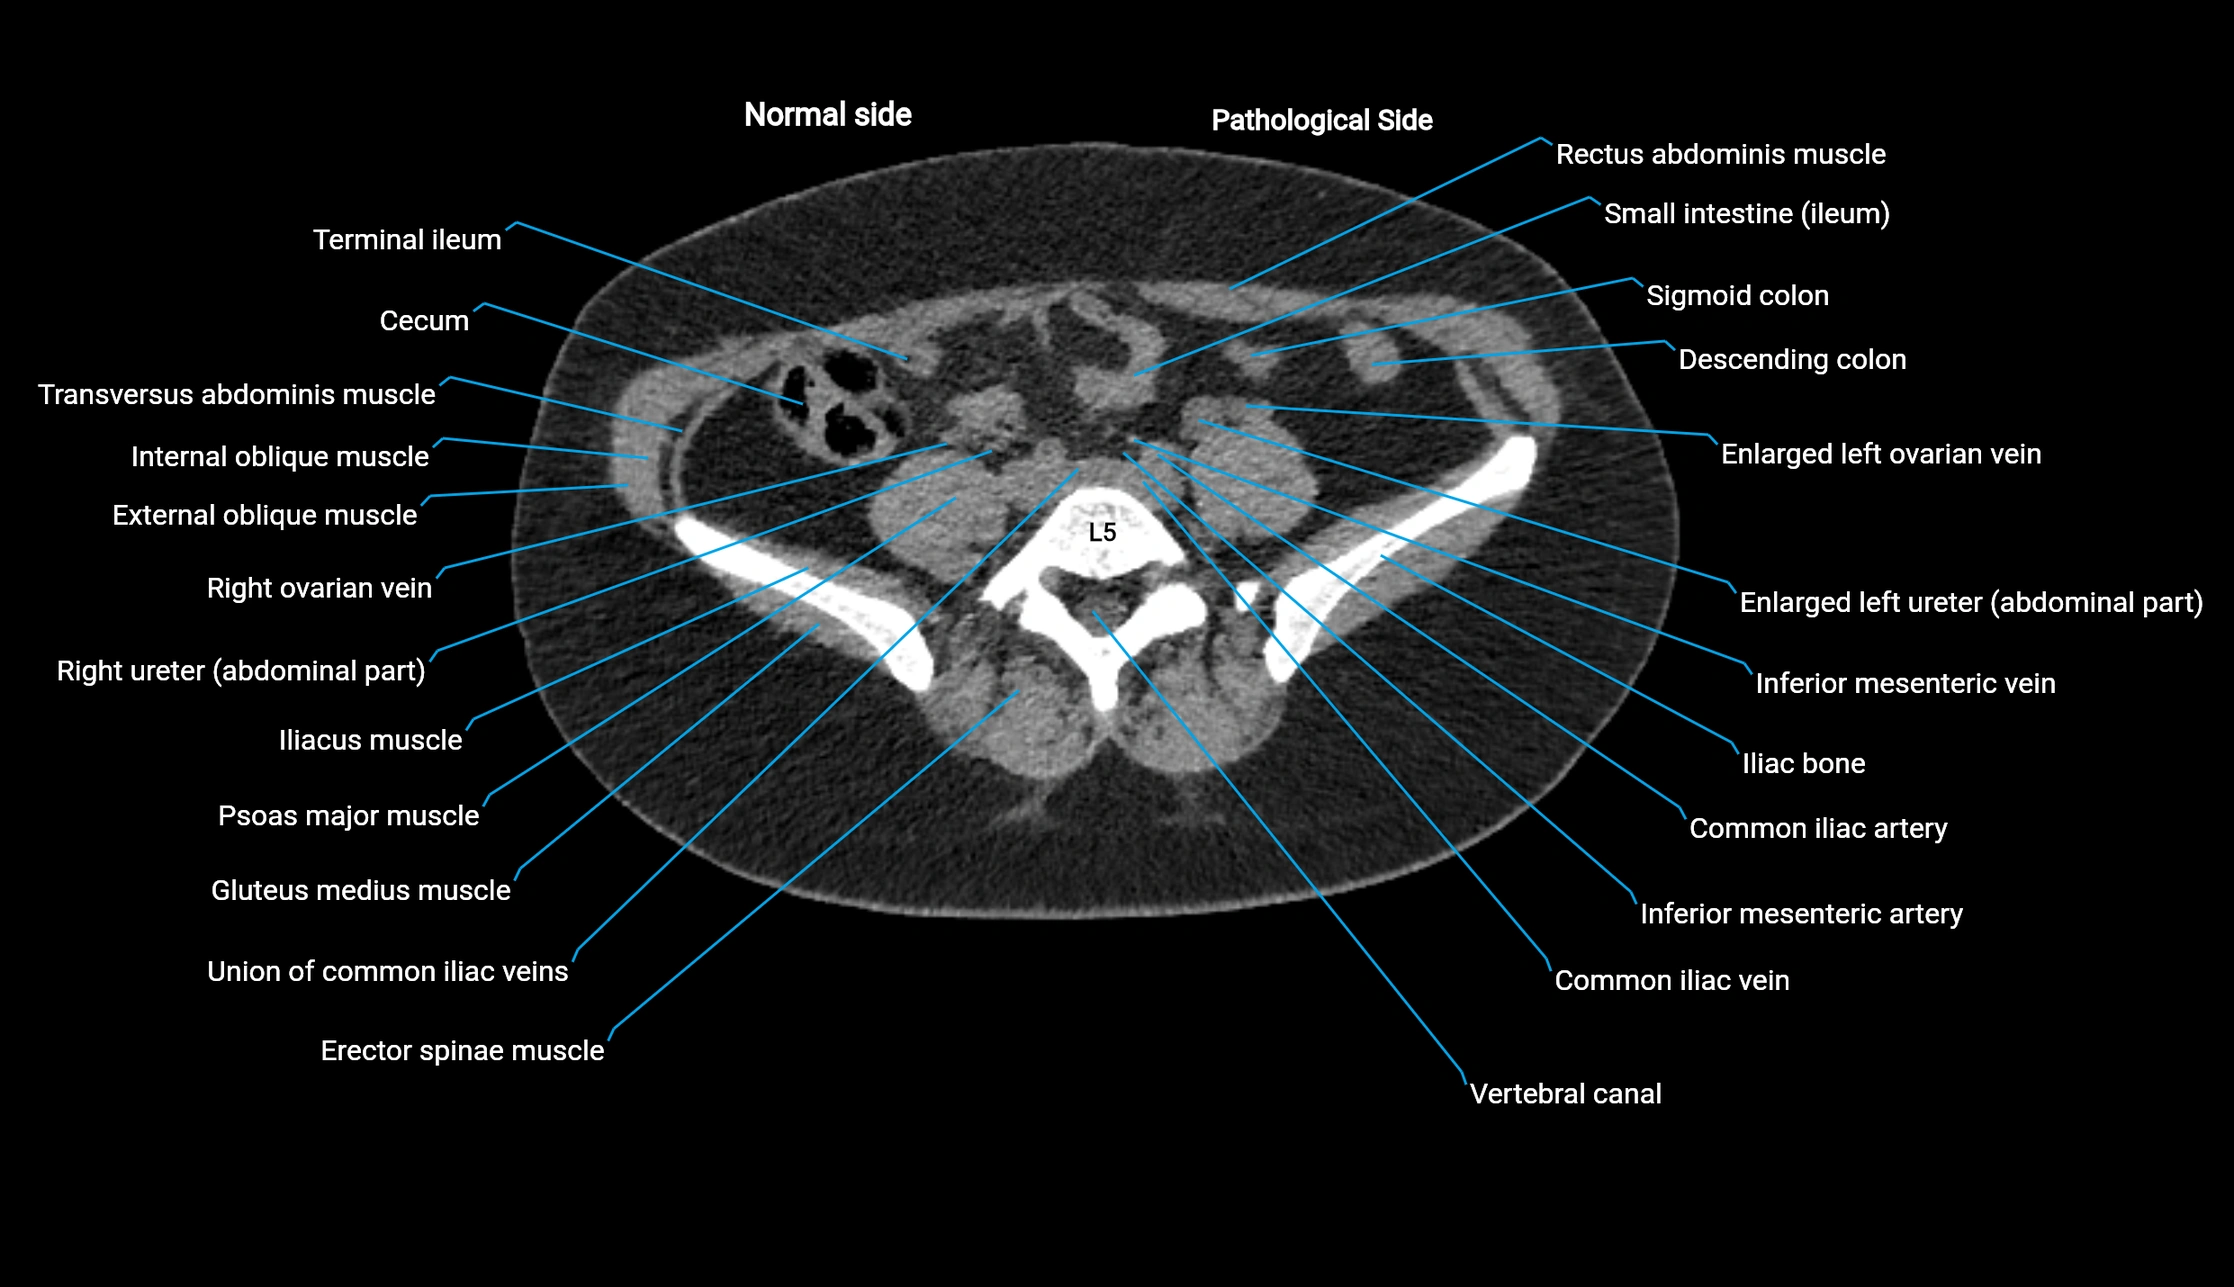

CT image

image